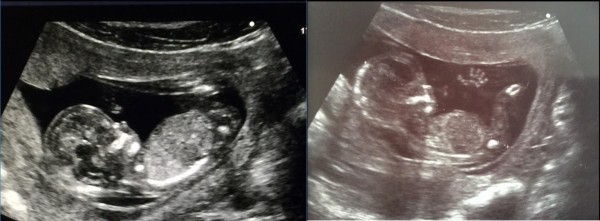

Neinvaziniams priklauso ultragarsiniai vaisiaus tyrimai. Vienas tokių yra atliekamas 11─13 nėštumo savaitę, kuris reikšmingas ne vien gimdymo datai, nėštumo trukmei, galimiems sklaidos sutrikimas, vaisiaus gyvybingumo ženklams nustatyti, bet ir vaisių skaičiui, placentos įsitvirtinimo vietai.

Ultragarsinis tyrimas 18─20 nėštumo savaitę yra palankus laikas įvertinti vaisiaus augimą, jo organų vystymąsi, placentą ir vaisiaus vandenis, vaisiaus raidos sutrikimus. Šiuo nėštumo laikotarpiu ultragarsu galima nustatyti daugiau kaip 50 proc. didžiųjų vaisiaus raidos sutrikimų, o kai kurių – net iki 90 proc.